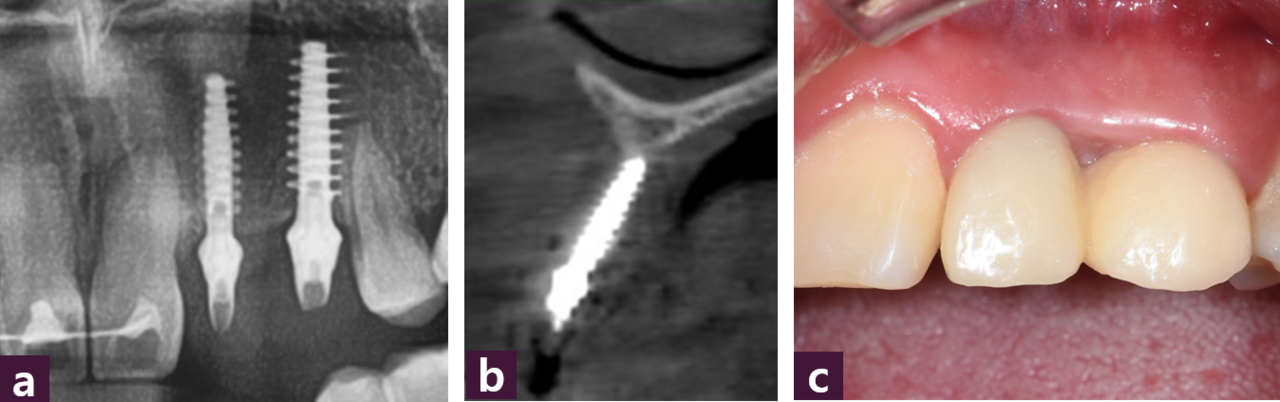

식립 직후 파노라마와 #22 임플란트의 CBCT 소견으로, concave 했던 순측면에 골 이식이 된 것을 볼 수 있다 [그림 17].

MagiCore 식립 5개월 후 temporary bridge를 장착한 파노라마, CBCT, 구강 내 사진 에서 장기적인 추적 관찰이 필요하지만 MagiCore 주위로 이식된 골이 유지되는 것을 볼 수 있다 [그림 18].